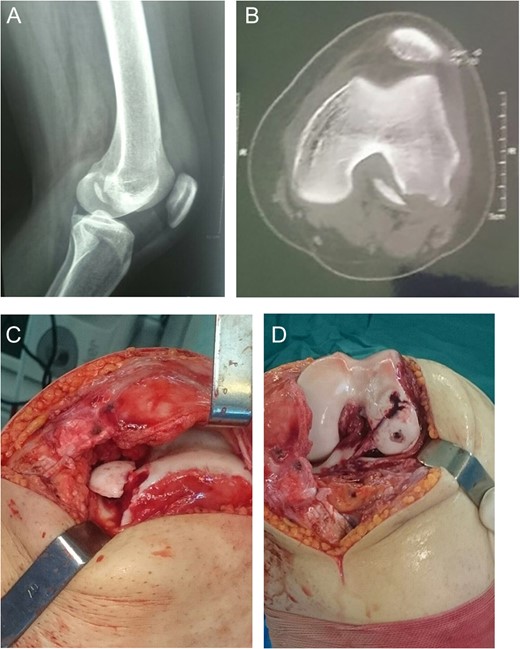

A 16-year-old male came with right knee pain and swelling after a twisting injury of the right knee while trying to break a wooden object with his left foot. Radiography showed a large OCF at the weight-bearing portion of the lateral femoral condyle [Fig.2A and B]. CT scan showed the bony avulsion from the medial facet of patella and the lateral femoral condyle OCF [Fig. 2C]. MRI showed lateral subluxation of patella [Fig. 2D]. Radiography, three months after the operation, showed complete union and the knee ROM was full [Fig. 2E and F].

Case 2. A and B Radiography showing lateral femoral condyle OCF and marked effusion. C, CT scan showing lateral patellar subluxation with medial patellar avulsion fracture and lateral femoral condyle OCF. D, MRI showing lateral patellar subluxation and marked joint effusion. E and F, 3 months postoperative radiography showing complete union.